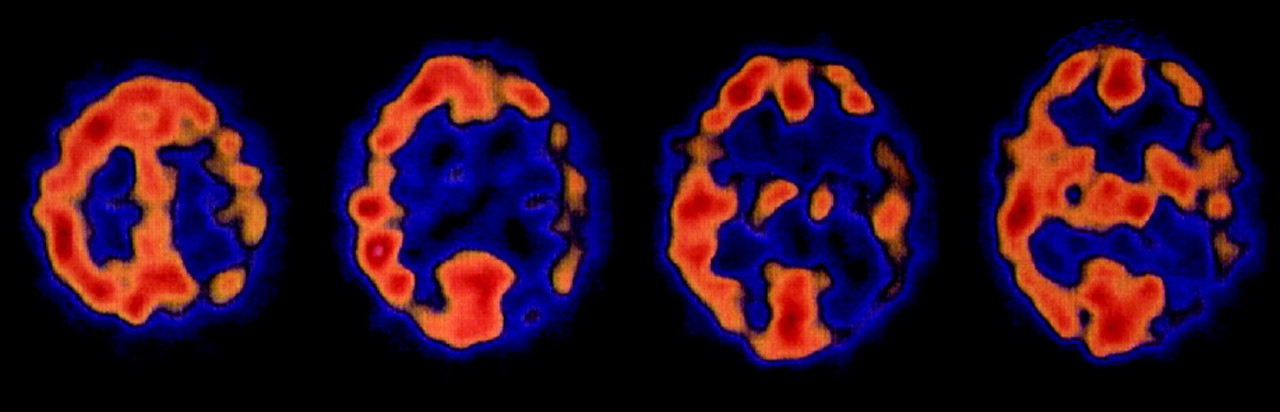

SPECT /宠物。

9名患者接受了核诊断测试的SPECT(5例)和宠物等(1例)(表e 1,上可用首页网站www.首页neurology.org)。在核磁共振成像中,颞叶是最常受影响(6例),其次是顶叶(5例)以及额叶和枕叶(4例)。

在疾病的进一步的课程他发达的视觉障碍,眩晕,手和脚的麻木。他取得了14 30分的细微精神状态检查。SPECT显示左脑灌注不足(图2)。脑电图显示在左额颞叶瓣的关注。病人发展幼稚的行为和言论的损失。一年后开始他的运动不能的哑,显示增加肌肉和肌阵挛。他仍然在这种状态下1年和后死亡疾病的2年。

在核磁共振,颞叶也经常在SPECT和PET的影响。

最早的SPECT发现我们的一个病人是一个低灌注的颞叶发病后3个月。患者检查后5个月或之后显示广泛的皮层的参与。然而,正如之前提到的其他作者,没有具体的损伤模式到目前为止已经发现了库贾氏症。24日,25